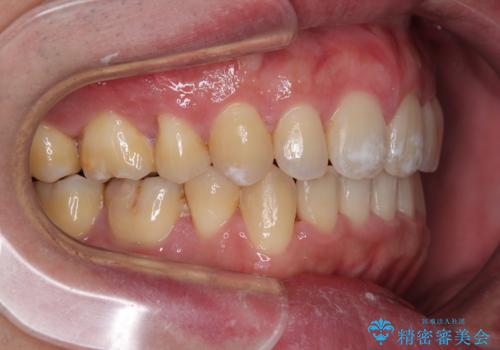

2年から2年半の治療期間を想定しており、予定通りの期間で無事に終了することができました。

唇や顎先に力を入れないなくてもスムーズに唇を閉じることができるようになりました。